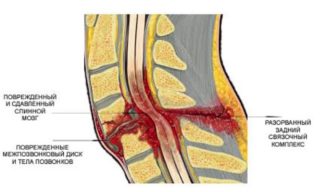

Злокачественная гемангиома в природе не встречается, что делает эту опухоль не такой страшной. Самым тяжёлым последствием считается перелом позвонков. Возникнуть может даже при минимальной нагрузке на позвоночник (как правило, нижний сегмент грудного отдела и верхний сегмент поясничного отдела). Случается перелом тела позвонка, непарного отростка задней поверхности дуги, поперечного отростка. Перелом может спровоцировать сдавливание спинного мозга. Возможен полный или частичный паралич нижних конечностей. Пережимание магистральных сосудов нарушает кровообращение. Как следствие, не избежать возникновения снижения чувствительности нижних конечностей, возможно появление мурашек, грозят симптомы недержания мочи.

Порой провоцируется внутреннее кровотечение. Состояние достаточно опасное. Возникает в результате разрыва тканей сосудистого образования на позвоночнике.

После вовлечения в разрушительный процесс значительной части кости позвонка повышается его уязвимость к механическому воздействию. Это становится причиной патологического перелома даже при легкой физической нагрузке.

Еще реже гемангиома позвоночника имеет неврологическую симптоматику. Неврологический дефицит может быть вызван следующими механизмами:

Открытое хирургическое вмешательство выполняется в тех случаях, когда возникает неврологический дефицит. То есть тогда, когда гемангиома достигла уже таких размеров и такого расположения, что привела к сдавлению нервных структур.